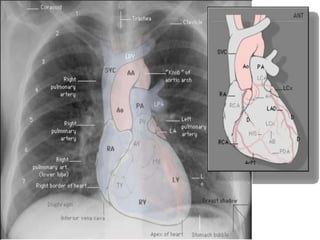

RADIOLOGIA DE TORAX

• Las estructuras evaluadas en Rx de tórax son:

• Cavidad torácica (piel, vértebras, costillas, esternon)

• Traquea

• Diafragma

• Espacio pleural

• Silueta cardiaca

• Pulmones y vasculatura pulmonar

Radiología de tórax normal

2- Diafragma

Límite inferior del tx

Ángulo costofrénico

Ángulo cardiofrénico

Excur.diafragm.3-7 cm

Derecho + ↑ izquierdo